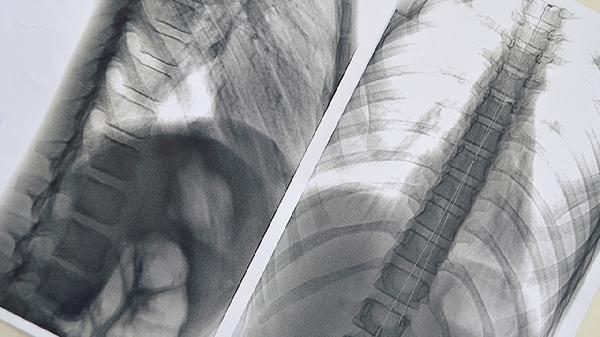

2、定期筛查很重要

低剂量CT能发现0.5厘米的肺结节,早期肺癌治疗几率可达90%。45岁以上吸烟者建议每年检查。